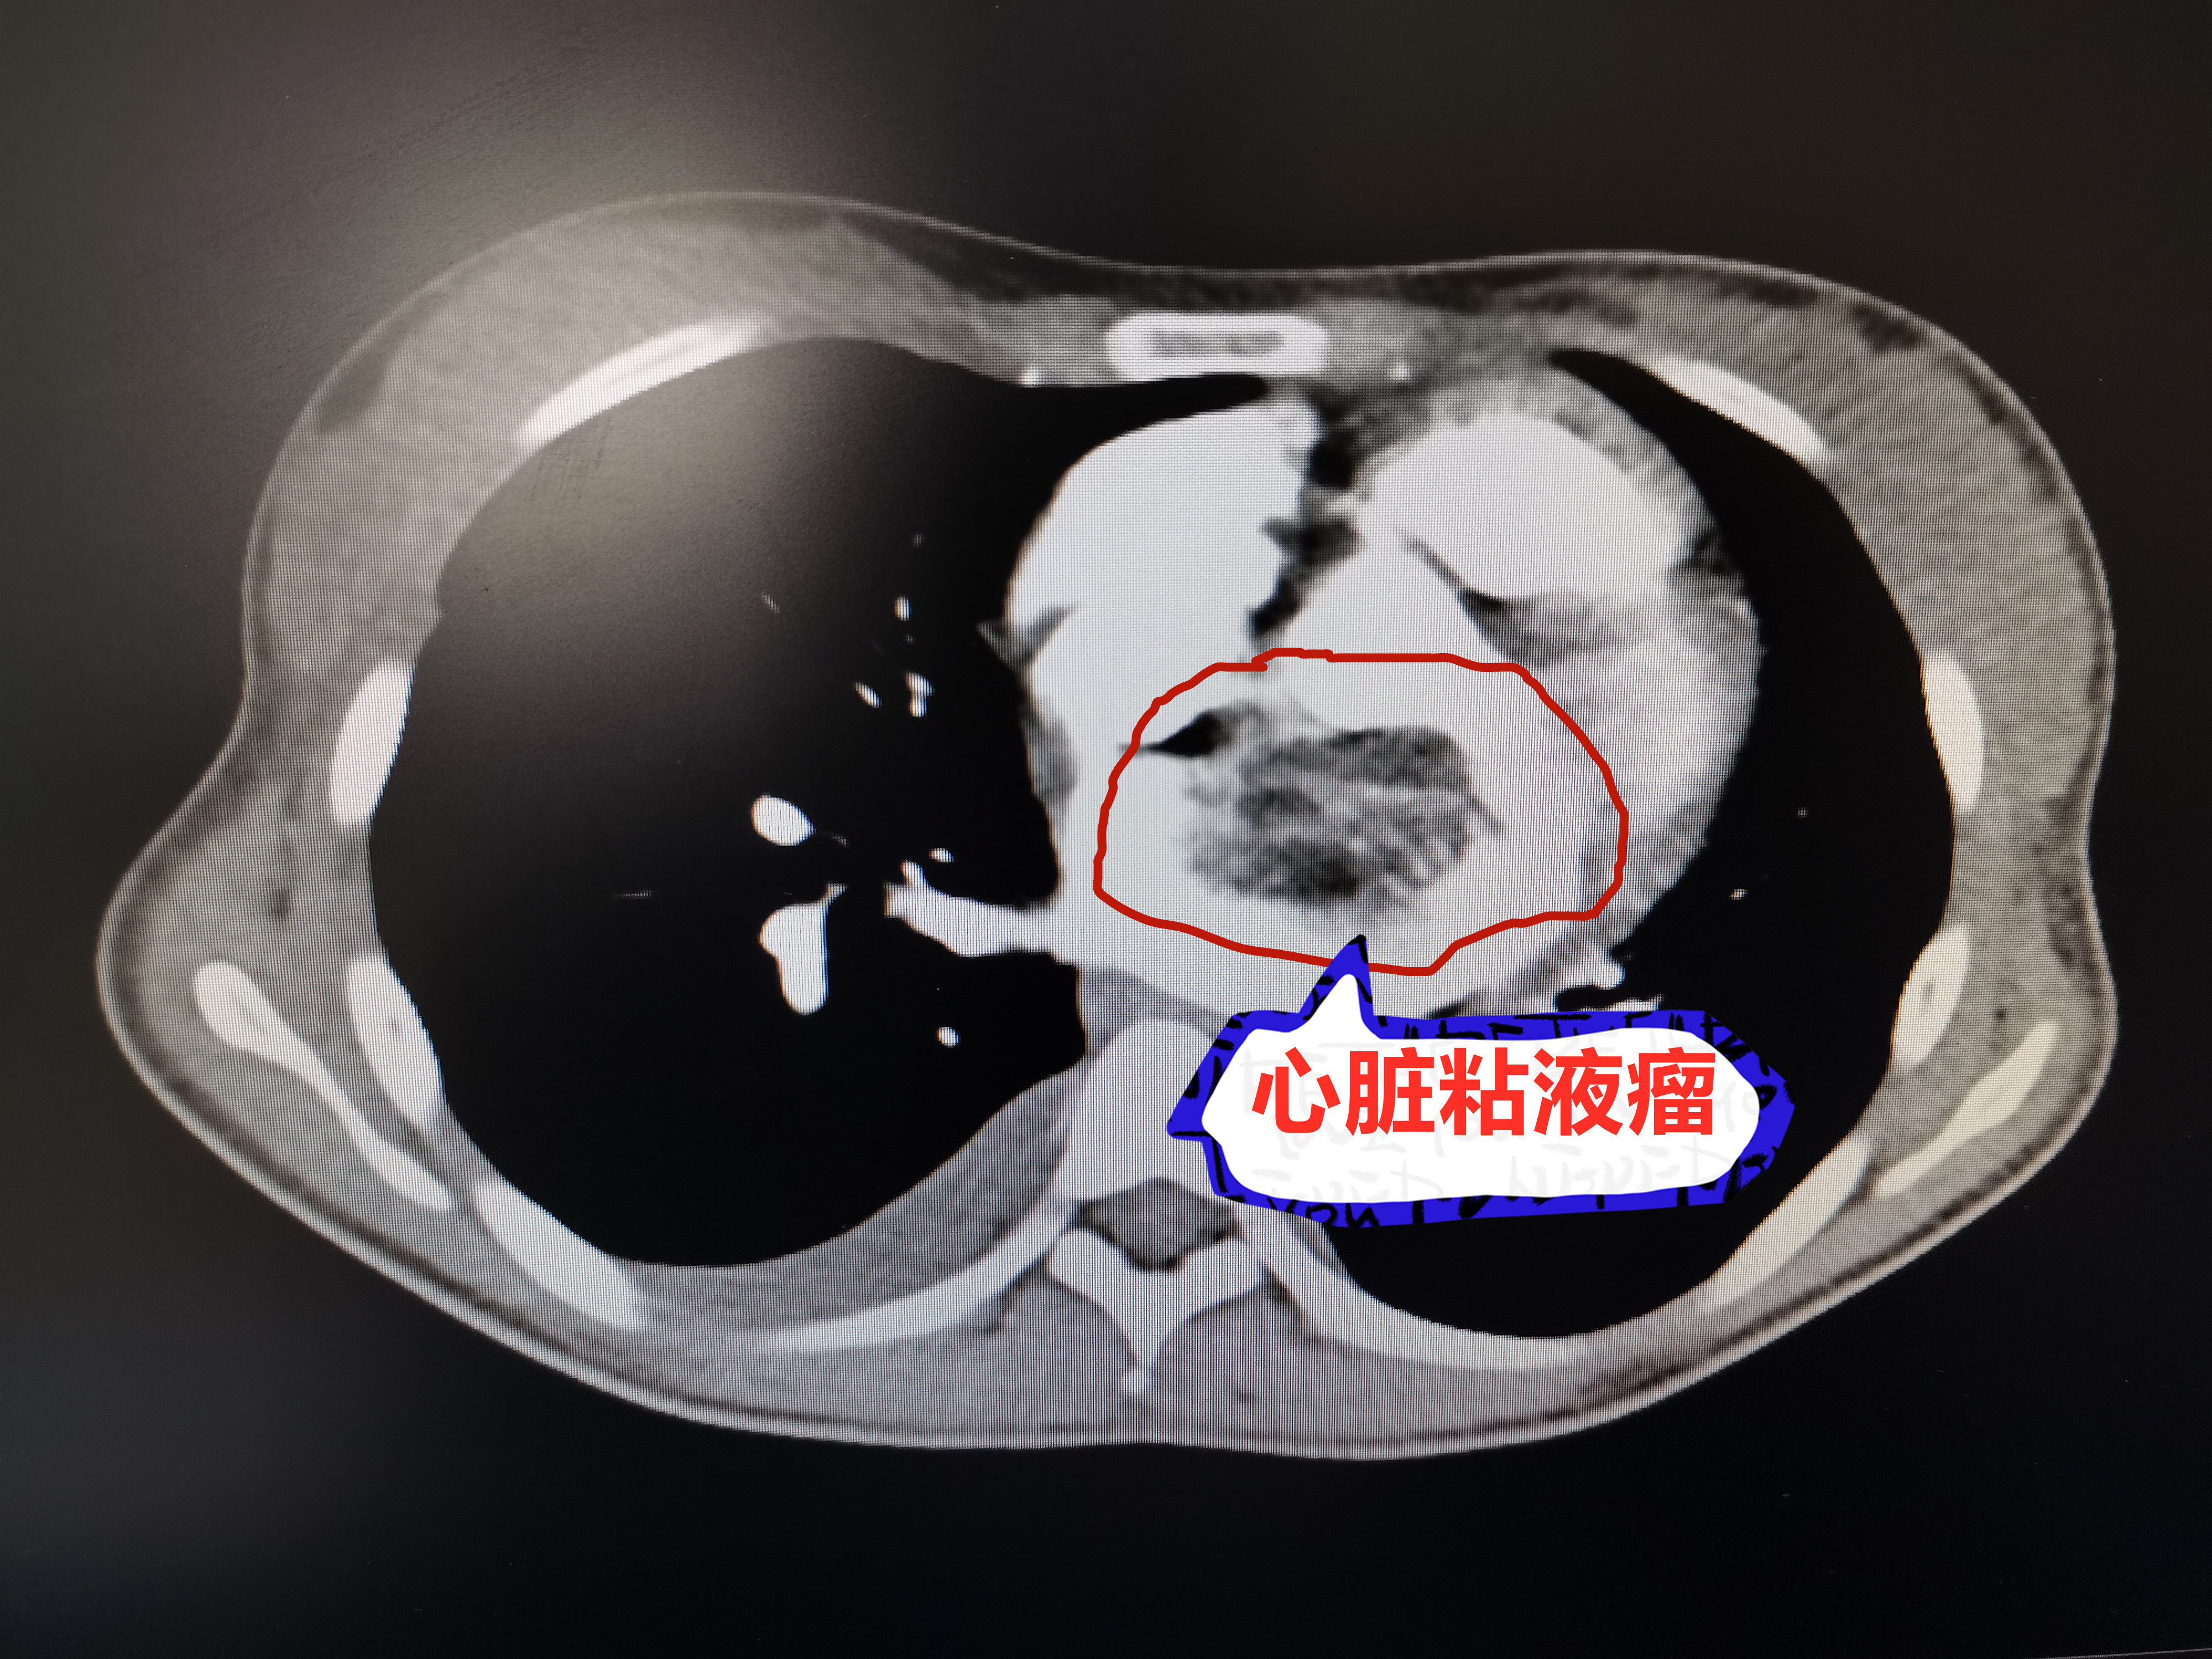

入院时CT检查结果

2020年7月底,婷婷因为双腿肿胀,且平卧后剧烈咳嗽,经就近医院检查,发现婷婷的心脏长了一个有鸡蛋大小的肿瘤,初步诊断为心脏粘液瘤,且出现心功能下降的情况。该肿瘤十分危险,患者随时可能因为肿瘤堵住心脏血流方向,导致心脏缺血而引发猝死。为及时治疗,婷婷父母立刻将她送到我院胸心血管外科住院治疗。

入院时婷婷的身体状况很糟糕,整个人半坐在病床上,根本不能平躺,双腿肿胀,面色苍白,嘴唇、指甲泛紫,足底也因供血不足开始出现紫红色花斑,尽管靠着药物在维持,但她的生命体征依然不稳定,情况十分危急。胸心血管外科主任韦舸立刻带领着医护团队多次进行病例讨论和评估,不断完善治疗方案。考虑到婷婷心功能衰竭的情况,通过利尿、强心等措施帮助婷婷将心脏功能恢复到一定程度后,在全麻体外循环下施行左心房肿物切除术。